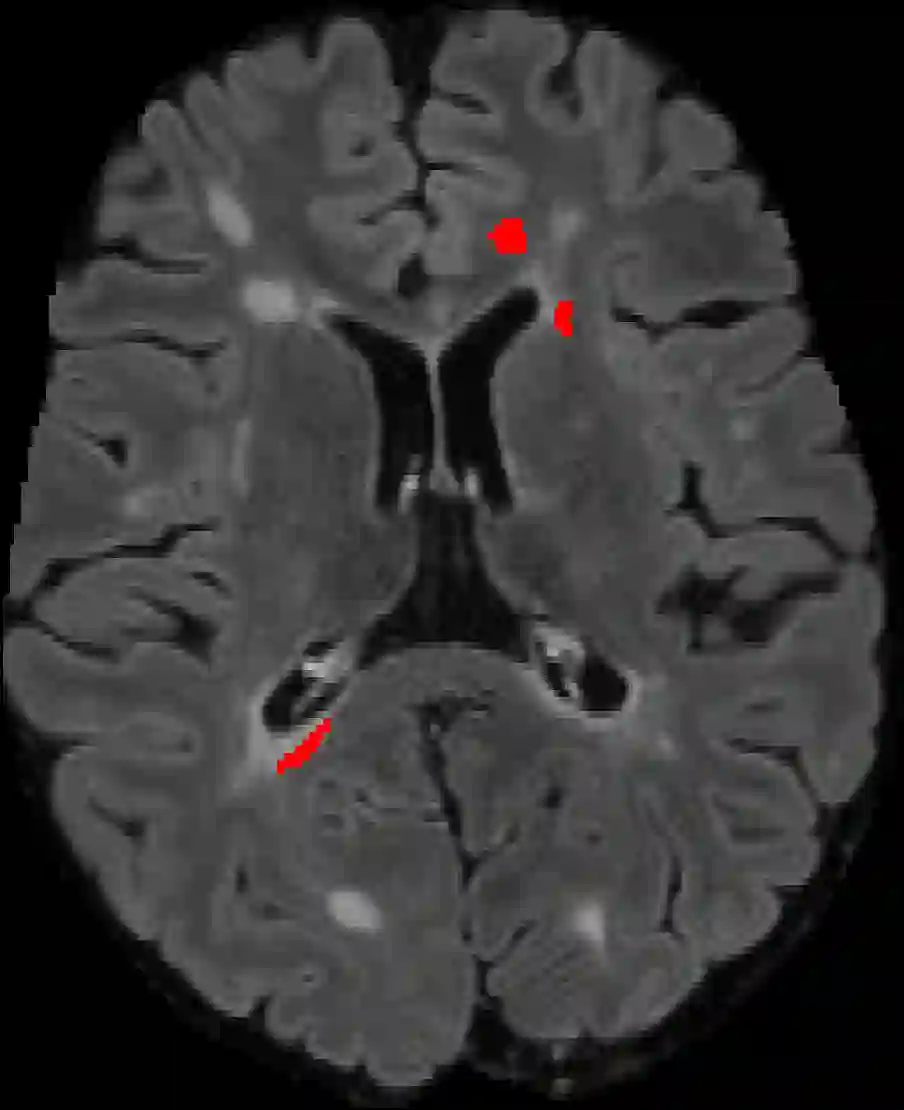

Assessment of lesions and their longitudinal progression from brain magnetic resonance (MR) images plays a crucial role in diagnosing and monitoring multiple sclerosis (MS). Machine learning models have demonstrated a great potential for automated MS lesion segmentation. Training such models typically requires large-scale high-quality datasets that are consistently annotated. However, MS imaging datasets are often small, segregated across multiple sites, with different formats (cross-sectional or longitudinal), and diverse annotation styles. This poses a significant challenge to train a unified MS lesion segmentation model. To tackle this challenge, we present SegHeD, a novel multi-dataset multi-task segmentation model that can incorporate heterogeneous data as input and perform all-lesion, new-lesion, as well as vanishing-lesion segmentation. Furthermore, we account for domain knowledge about MS lesions, incorporating longitudinal, spatial, and volumetric constraints into the segmentation model. SegHeD is assessed on five MS datasets and achieves a high performance in all, new, and vanishing-lesion segmentation, outperforming several state-of-the-art methods in this field.